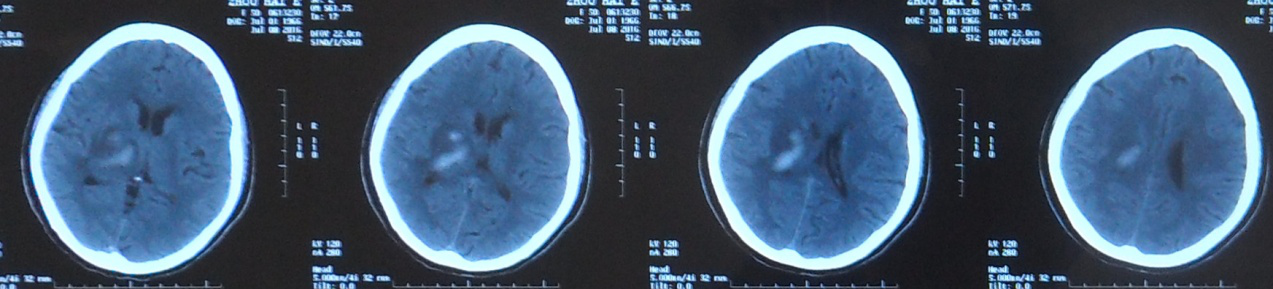

2016年10月05日头部CT片示:左侧丘脑区不规则片状高密度影,周围见水肿带围绕,左侧侧脑室受压变窄,右侧丘脑区片状低密度灶,双侧额叶小点片低密度灶。

2016年10月05日头部CT片